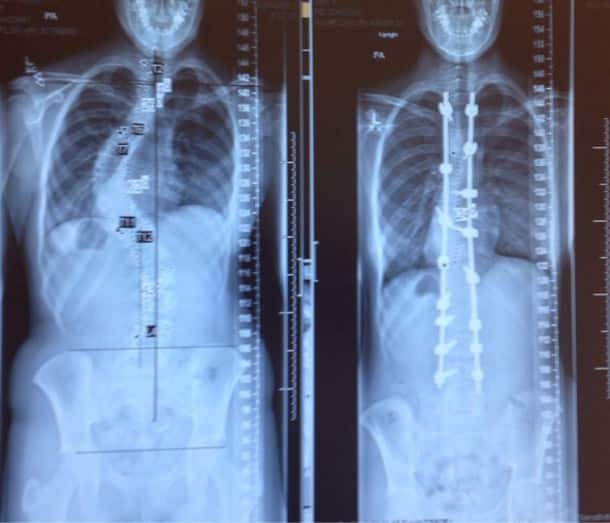

Un scoliose avant / après un traitement au laser